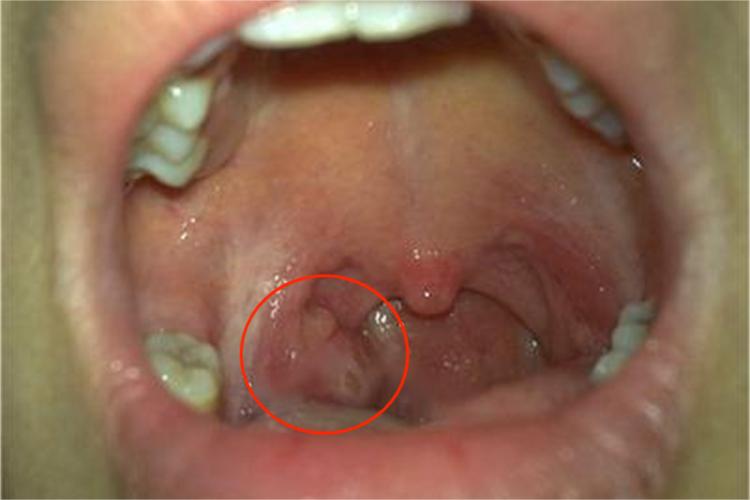

扁桃体癌通常先表现为咽部不适、异物感,随后咽痛加剧,可出现吞咽困难。同时,检查可见扁桃体肿大,表面溃烂,呈结节状隆起,易出血,可与周围组织粘连。